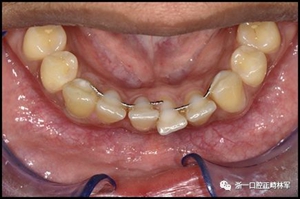

一顆或兩顆尖牙位置的橫向變化可能發(fā)生在與每顆牙齒粘合的小弓絲上,并且在極軟弓絲(圖3)和柔性螺旋弓絲(圖4)上都可以看到。較大直徑的弓絲會產(chǎn)生不同類型的橫向變化。較硬的弓絲與更小的弓絲相比,在尖牙之間產(chǎn)生更多的相關(guān)關(guān)系。弓絲的扭曲會導(dǎo)致尖牙的往復(fù)運(yùn)動和弓形的歪斜(圖5)。相對較硬弓絲的向下偏斜可以通過尖牙產(chǎn)生擴(kuò)張(圖6)。

圖3.極軟弓絲完全完好,在多個(gè)空間平面上的拱形歪斜,右側(cè)尖牙的面部傾斜以及右側(cè)側(cè)切牙和中切牙在相反方向上的扭矩:A,頰面視圖; B,咬合面視圖。